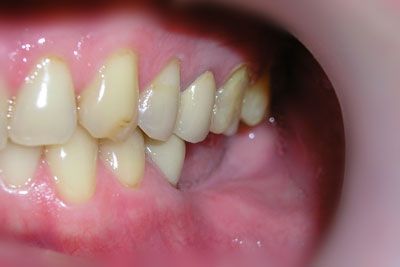

На прием к стоматологу-ортопеду пришел пациент с жалобой на отсутствие нижних коренных зубов и неудобство пережевывать пищу. При осмотре выяснилось, что отсутствующие нижние моляры (36 и 37 зубы - по международной классификации) удалены два года тому назад.

От протезирования с помощью мостовидной конструкции (в этом случае обтачиваются соседние здоровые зубы и на них ставятся опорные коронки) он отказался. Для выполнения надежной мостовидной конструкции нам пришлось бы обточить три зуба 34, 35 и 38, два из которых еще и депульпировать. С предложением установить два винтовых имплантата и последующем изготовлением металлокерамических коронок пациент согласился. Под местной анестезией была произведена установка двух винтовых имплантатов Astra Tech с одномоментной постановкой формирователей десны.